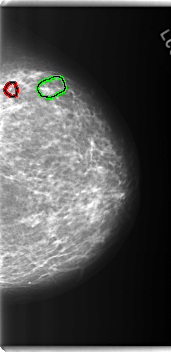

C_0280_1.LEFT_MLO

LEFT_MLO LINES 5920 PIXELS_PER_LINE 3192 BITS_PER_PIXEL 12 RESOLUTION 50 OVERLAY

FILE: C_0280_1.LEFT_MLO.OVERLAY

TOTAL_ABNORMALITIES 4

ABNORMALITY 1

LESION_TYPE MASS SHAPE ARCHITECTURAL_DISTORTION MARGINS SPICULATED

ASSESSMENT 4

SUBTLETY 4

PATHOLOGY BENIGN

ABNORMALITY 2

LESION_TYPE CALCIFICATION TYPE PLEOMORPHIC DISTRIBUTION CLUSTERED

SUBTLETY 5

ABNORMALITY 3

ASSESSMENT 3

ABNORMALITY 4

LESION_TYPE CALCIFICATION TYPE AMORPHOUS DISTRIBUTION CLUSTERED

SUBTLETY 3